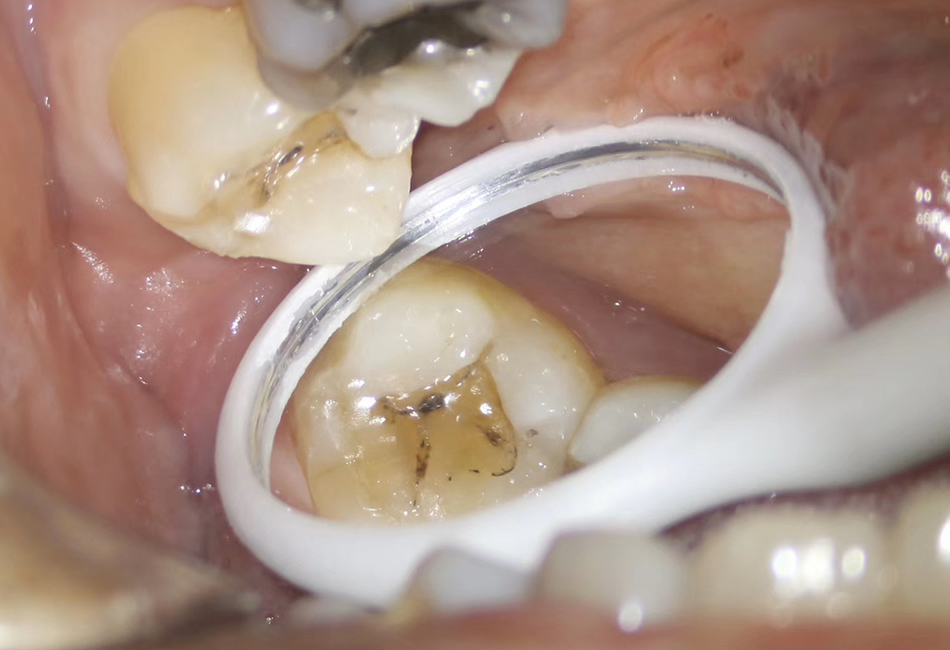

热烈欢迎青海爱心口腔杨院长及其同事一行,到文鸣口腔学习、交流显微仿生修复技术!在观看了杨院长亲自体验的两颗仿生修复直播后,其同事说:这种技术太棒了,颠覆了她对补牙的三观!极致微创、文鸣仿生,致力于让更多人不把牙齿磨小做套,在路上……